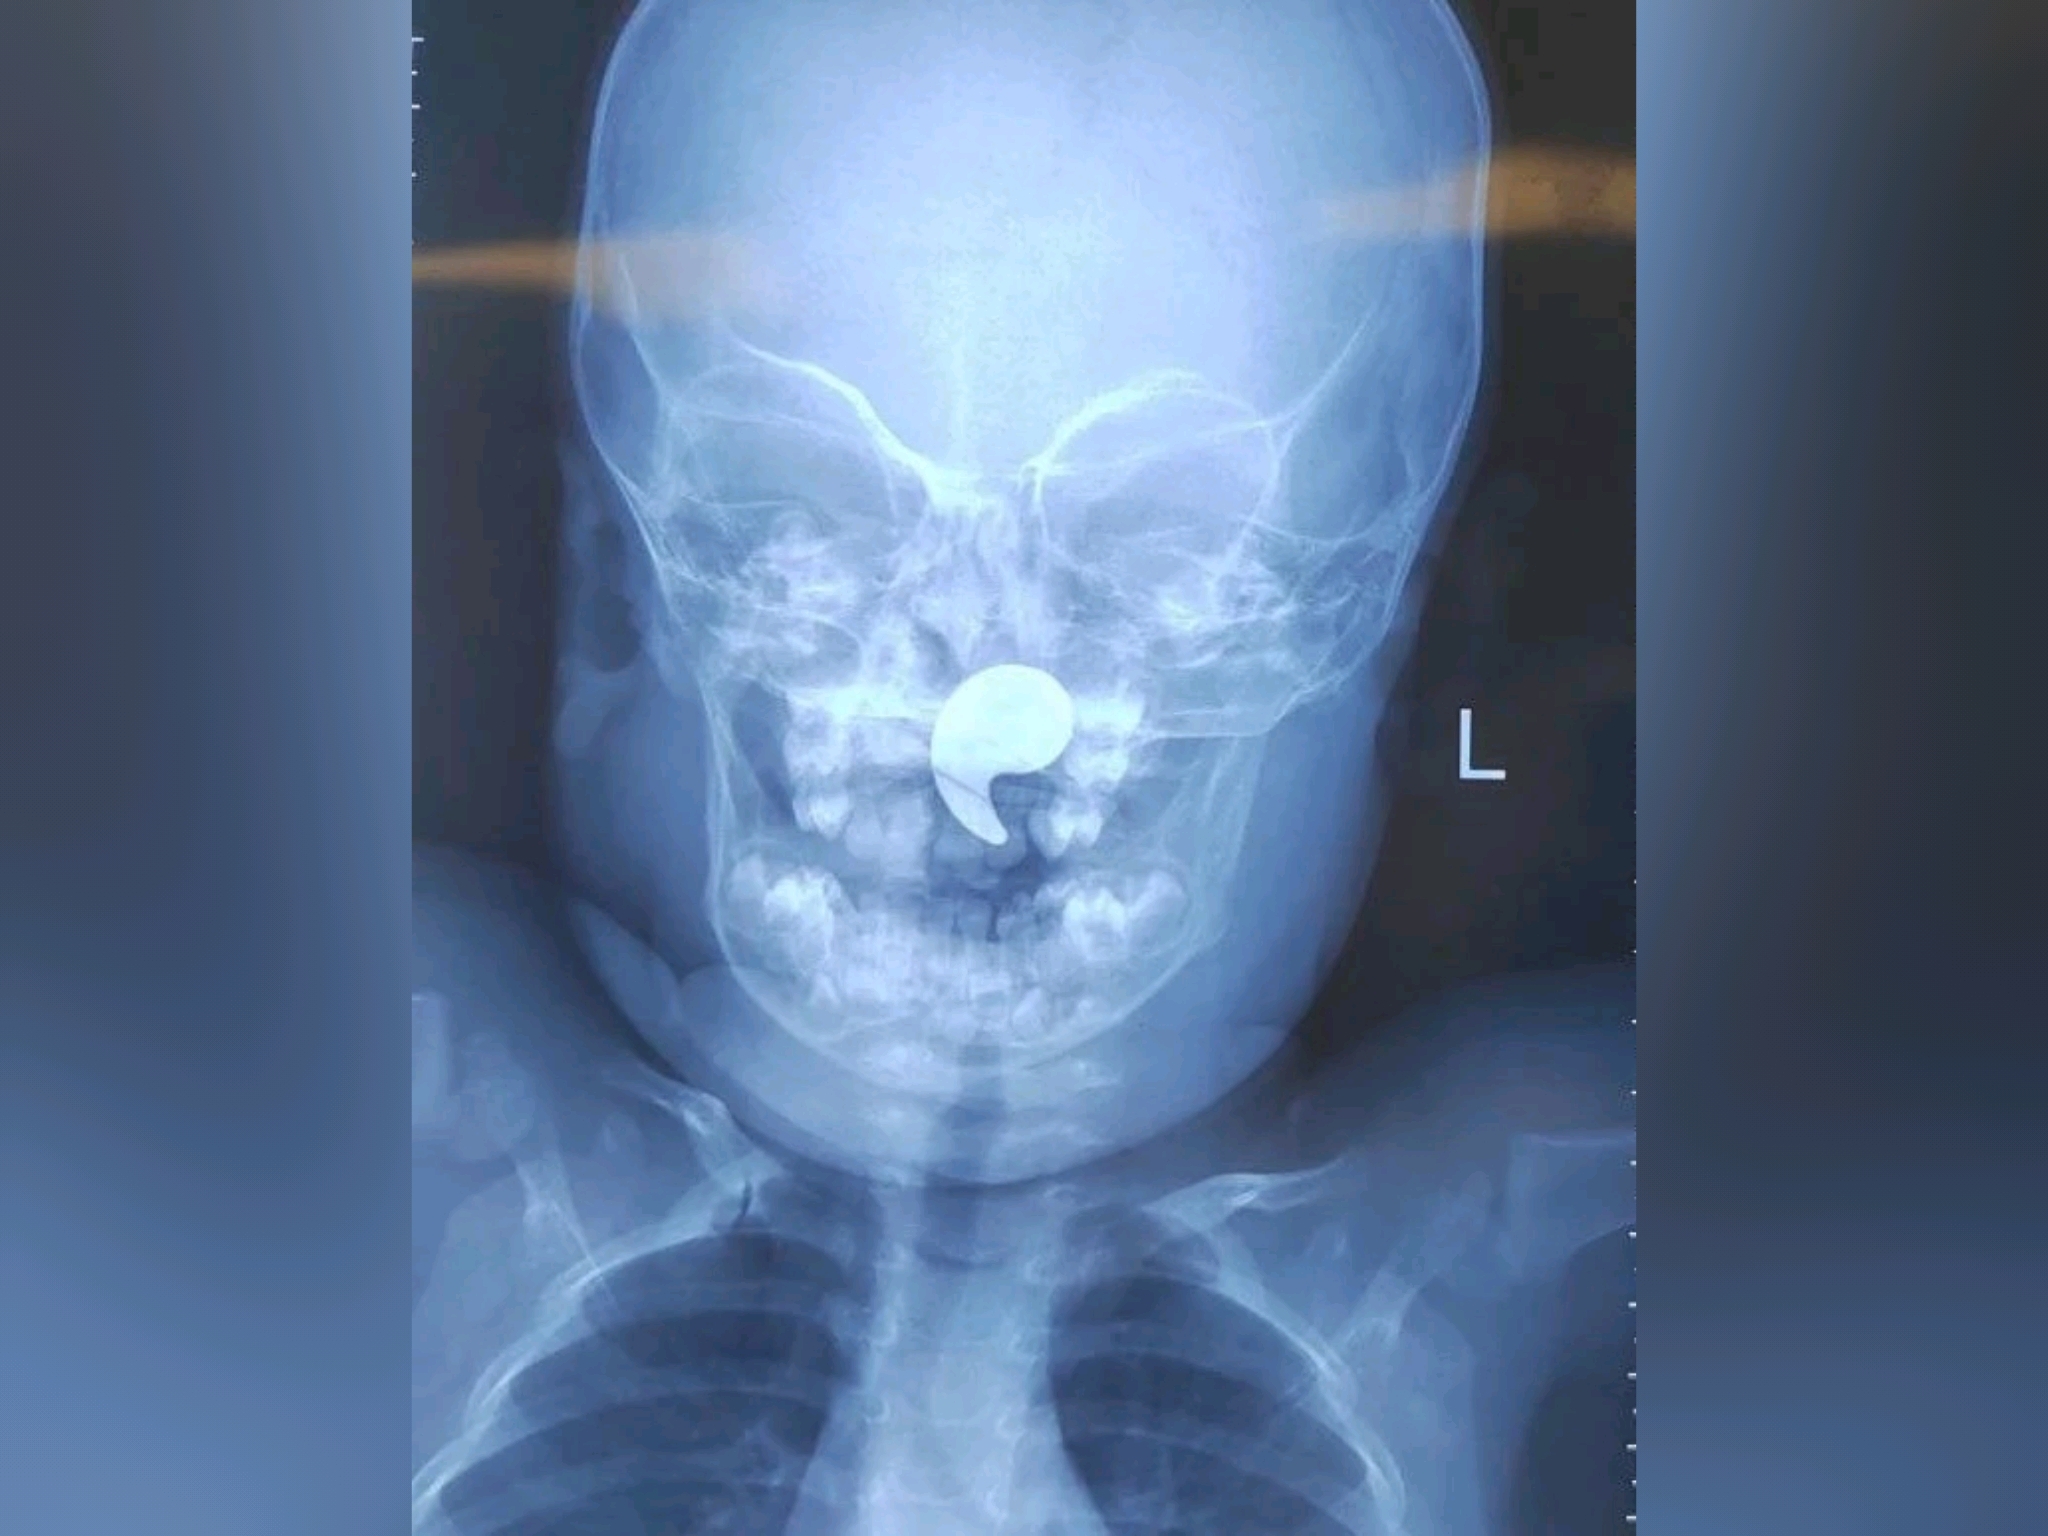

К тому моменту малышка уже жаловалась на боль в горле, отказывалась от еды, а слюнотечение стало активным. Врачи сделали рентген — на снимке отчетливо просматривалось инородное тело. Девочку немедленно госпитализировали в оториноларингологическое отделение ВОДКБ №1. Оперировала ребенка дежурный врач отделения Марина Перепечена. Под общей анестезией, с помощью эндоскопического контроля, она успешно удалила магнит. Уже через сутки девочку выписали домой. Теперь за её здоровьем наблюдает педиатр по месту жительства.